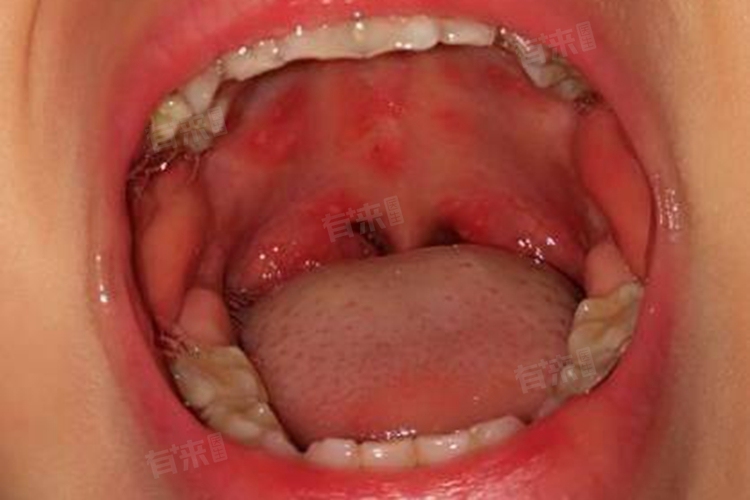

当口腔内出现疱疹时,通常是由疱疹病毒感染引起的,尤其是单纯疱疹病毒。针对这种情况,可以配合医生采取保持口腔清洁、抗病毒治疗、镇痛治疗等措施进行治疗和护理。